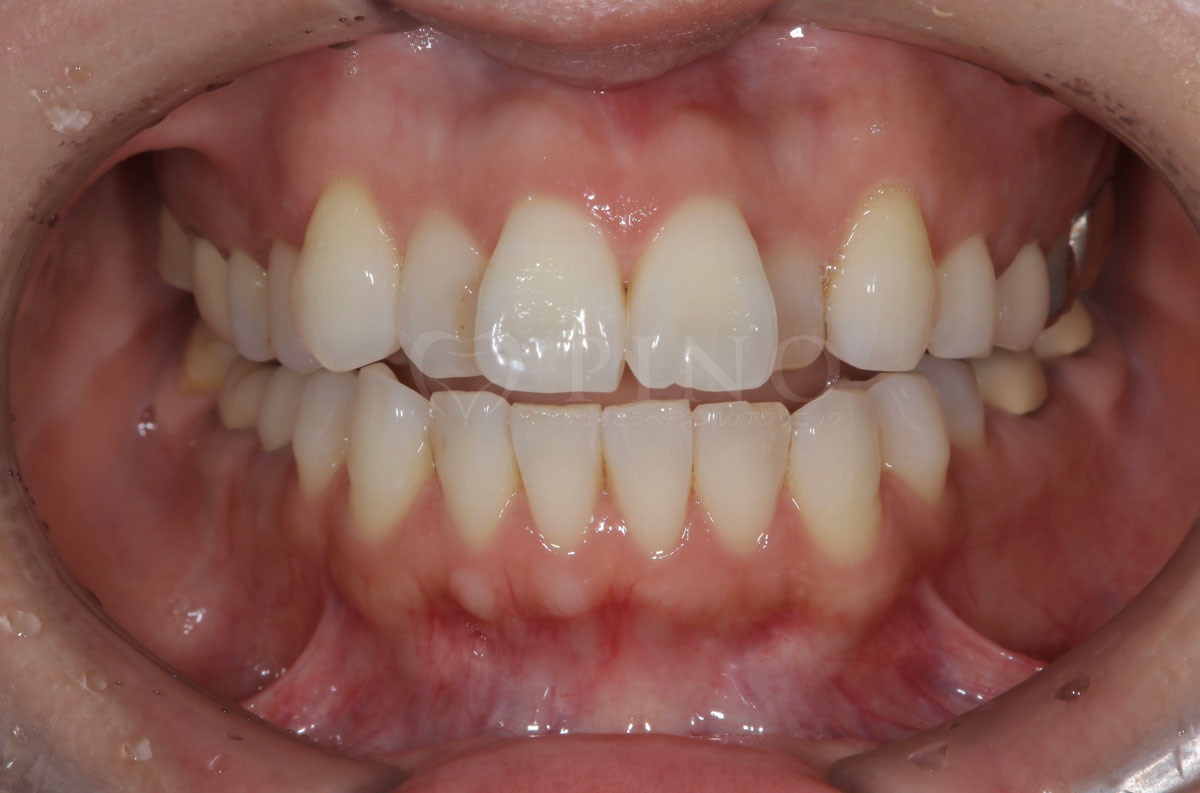

症例4:噛み合わせが深く、下の歯が見えないのが気になる(10代女性)

主訴 噛み合わせが深い、下の歯が見えない 診断名 過蓋咬合(かがいこうごう) 治療方法 マウスピース全顎矯正 抜歯 なし オルソパルス なし 治療期間 1年1ヶ月 費用 746,000円 副作用・注意点 矯正後の後戻りを防ぐためリテーナーの使用が必要となる -